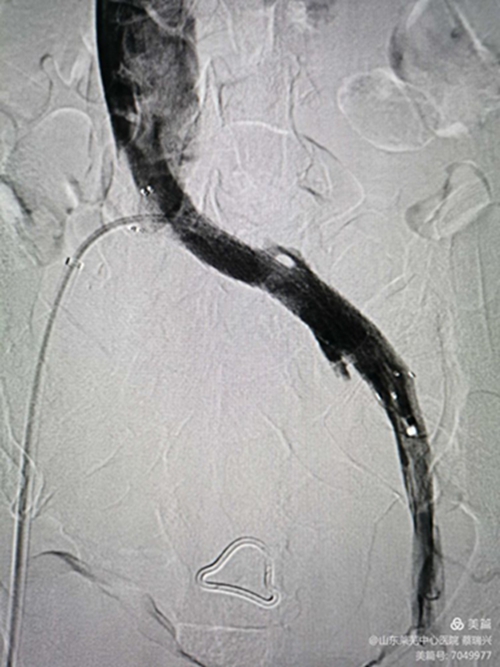

釋放支架,行后擴(kuò)張,球囊有“腰征",且很窄,考慮閉塞段像"噗"一樣。

噗征

后擴(kuò)滿意后

再造影見狹窄消失,血流順暢。